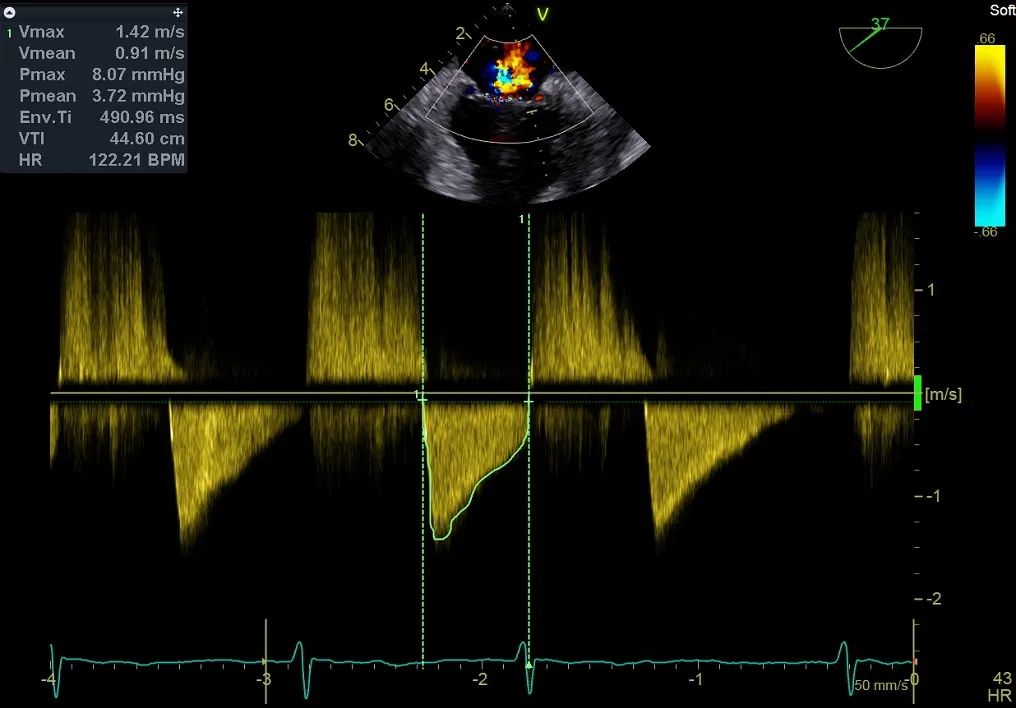

术前行经食道超声评估:继发性二尖瓣反流,反流程度4+;二尖瓣有效反流口面积(EROA) 0.81 cm²,缩流颈宽度18 mm,反流容积112.36ml,二尖瓣瓣口面积5.06 cm²,平均跨瓣压差5 mmHg,二尖瓣前叶(A2)长度15mm,二尖瓣后叶(P2)长度9 mm;左房内径54mm,左室收缩末期内径50mm,左室射血分数43%,肺动脉压83 mmHg。

再次反复测试第二枚二尖瓣钳夹的稳定性,超声复查提示二尖瓣反流明显改善,平均跨瓣压差4 mmHg